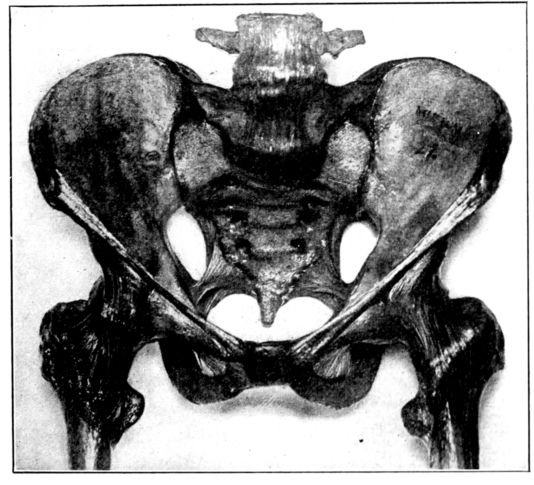

Viewed in its entirety, the pelvis is an irregularly constructed, two-storied, bony cavity, or canal, situated below and supporting the movable parts of the spinal column, and resting upon the femora or thigh bones. (Fig. 1, A. and B.).

Four bones enter into the construction of the pelvis: the two hip bones or ossa innominata, on the sides and in front with the sacrum and coccyx behind.

The innominate bones (ossa innominata), symmetrically placed on each side, are broad, flaring and scoop-shaped. Each bone consists of three main parts, which are separate bones in early life, but firmly welded together in adults: the ilium, ischium and pubis. The ilia are the broad, thin, plate-like sections above, 20their upper, anterior prominences, which may be felt as the hips, are the anterior superior spinous processes used in making pelvic measurements. The margins extending backward from these points are termed the iliac crests.

The ischii are below and it is upon their projections, known as the tuberosities, that the body rests when in the sitting position, and which also serve as landmarks in pelvimetry. The pubes form the front of the pelvic wall, the anterior rami uniting in the median line by means of heavy cartilage and forming the symphysis pubis.

The sacrum and coccyx behind are really the termination of the spinal column, the sacrum consisting, usually, of five rudimentary vertebrae which have fused into one bone. It sometimes consists of four bones, sometimes six, but more often of five. The sacrum completes the pelvic girdle behind by uniting on each side with the ossa innominata by means of strong cartilages, thus forming the sacro-iliac joints. The spinal column rests upon the upper surface of the sacrum. The coccyx, a little wedge-shaped, tail-like appendage, which ordinarily has but slight obstetrical importance, extends in a downward curve from the lower margin of the sacrum, to which it has a cartilaginous attachment, the sacro-coccygeal joint. This joint between the sacrum and coccyx is much more movable in the female than in the male pelvis.

We find, therefore, that although the pelvis constitutes a rigid, bony, ringlike structure, there are four joints: the symphysis pubis, the sacro-coccygeal, and the two sacro-iliac articulations. As the cartilages in these joints become somewhat softened and thickened during pregnancy, because of the increased blood supply, they all permit of a certain, though limited amount of motion at the time of labor. This provision is of considerable obstetrical importance, since the sacro-coccygeal joint allows the child’s head to push back the forward-protruding coccyx, as it passes down the birth canal, thus removing what otherwise might be a serious obstruction. And when, as is sometimes necessary, because of a constricted inlet, the pubic bone is cut through (the operation known as pubiotomy), the hingelike motion of the sacro-iliac joint permits of an appreciable spreading of the two hip bones and a consequent widening of the birth canal.

A. Normal female Pelvis.

B. Normal male Pelvis.

Fig. 1.—Normal Pelves. Note the broad, shallow, light construction of the female pelvis, A, as compared with the more massive male pelvis, B.

The normal male pelvis is deep, narrow, rough and massive as compared with the female structure (see Fig. 1.), and the angle of the pubic arch, formed by the two pubic bones, is deeper and more acute in the male than in the female skeleton.

The normal female pelvis, on the other hand, is light, broad, shallow, smooth and large, giving evidence of the infinite wisdom and skill that entered into constructing it for the high purpose it was designed to serve.